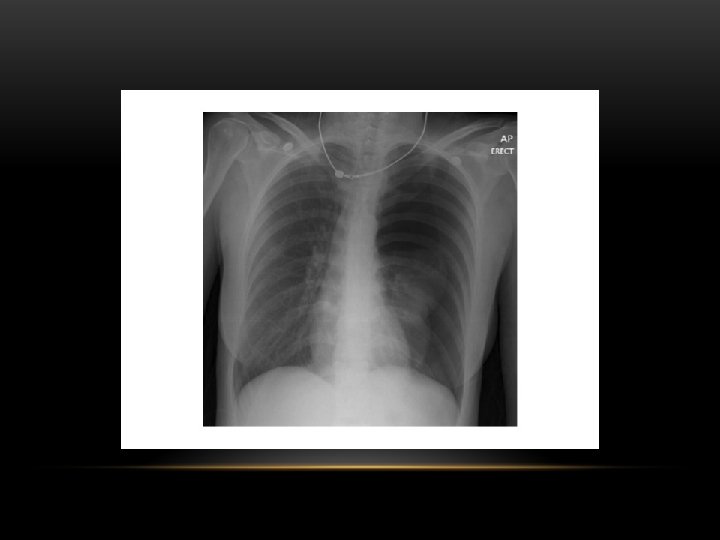

Spontaneous Pneumothorax • Air in pleural space • Lung margin • "Normal lungs": Note the radiolucency of atelectatic lung is the same as the opposite lung